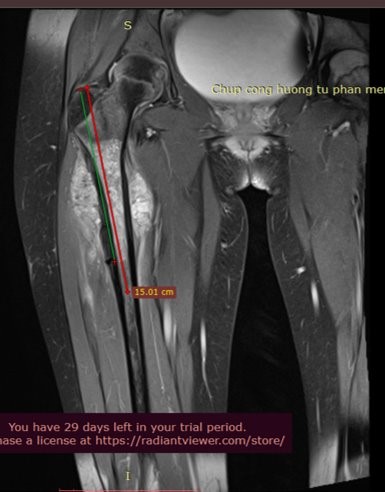

Cháu Khánh Thơ, 12 tuổi phát hiện ung thư xương chày chân trái giai đoạn 2B từ giữa năm 2021. Sau khi phẫu thuật cắt bỏ toàn bộ khối u ở khớp gối, bảo tồn chi, cháu điều trị hóa chất bổ trợ 4 chu kỳ. Tuy nhiên, chỉ hơn 1 năm sau, bé Thơ đã di căn phổi.

Tìm hiểu về quá trình điều trị của bệnh nhân, GS.TS.BS Trần Trung Dũng – GĐ Trung tâm Chấn thương Chỉnh hình và Y học thể thao (CTCH) Vinmec cho biết, mặc dù bệnh nhân có kết quả mổ rất tốt, nhưng sử dụng hóa trị bổ trợ không đủ liều là nguyên nhân dẫn đến di căn phổi nhanh như nhiều trường hợp khác.